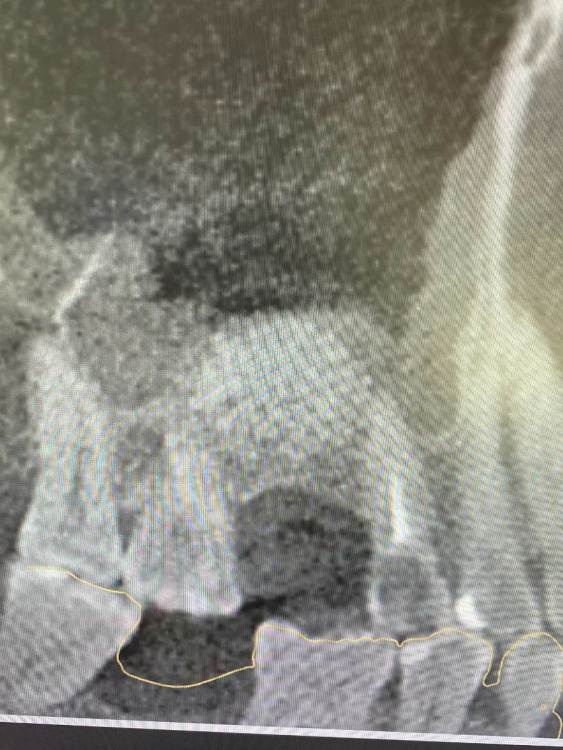

kamranchick Опубликовано 5 августа, 2021 Поделиться Опубликовано 5 августа, 2021 Приветствую, первый раз сталкиваюсь с подобной ситуаций стандартная ситуация, ОСЛ с использованием чистого апатос кортикал, ожидание 5 месяцев,заживление без осложнений сегодня начинаю сверление, и один сплошной фиброз какой прогноз коллеги? стоит ждать чуда? прилагаю снимки Ссылка на комментарий

NickBulin Опубликовано 30 августа, 2021 Поделиться Опубликовано 30 августа, 2021 05.08.2021 в 18:09, kamranchick сказал: Приветствую, первый раз сталкиваюсь с подобной ситуаций стандартная ситуация, ОСЛ с использованием чистого апатос кортикал, ожидание 5 месяцев,заживление без осложнений сегодня начинаю сверление, и один сплошной фиброз какой прогноз коллеги? стоит ждать чуда? прилагаю снимки Была подобная картина на контрольном КТ через 5 месяцев после ОСЛ, решили подождать еще 4 месяца У пациента жалоб нет?) Ссылка на комментарий

Александр07 Опубликовано 17 сентября, 2021 Поделиться Опубликовано 17 сентября, 2021 Использую апатос микс, у двух пациентов и в трёх синусах у них такая ситуация была- при раскрытии все рыхлое, гранулы не интегрированы вперемежку с грануляциями для себя вывел что в этих условиях (исходно кости мало 1-2 мм, поэтому делалось в два этапа ) вилимо материал плохо работает и надо с ауто мешать или переходить на биоосс , не помню было с ним подобное или нет вооьще лусше мешать конечно, но как то бывает не охота на низ идти за забором а с наружной стенки бывает не много собрать получается Ссылка на комментарий